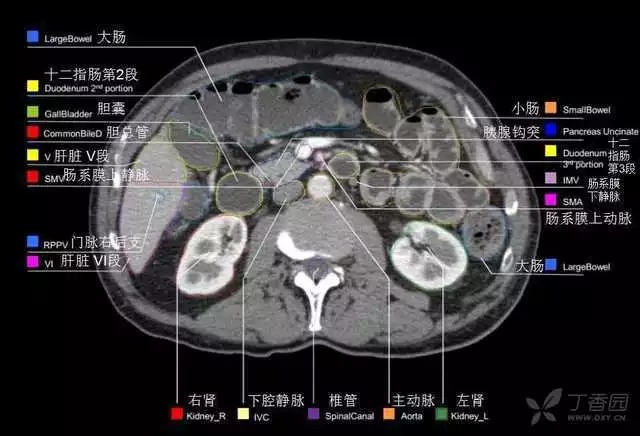

腹部肝脏高清CT断层的图谱

全腹部高清CT图谱,淋巴结彩色图谱,血管解剖图谱大汇总!